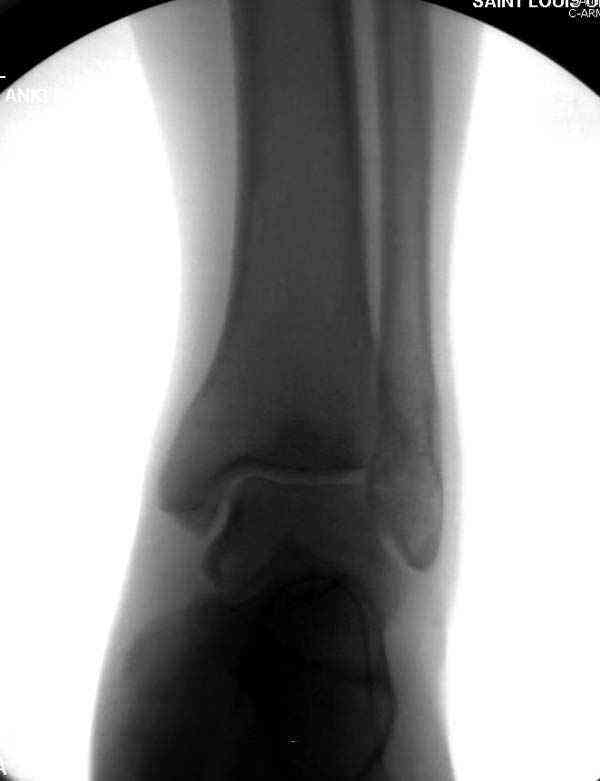

Случай прошлого года:пациентка-молодая ,крупная женщина ,30лет.Травма в начале апреля 2009г-пронационный перелом лодыжек с подвывихом стопы.Ко мне обратилась через 35 дней,прооперирована 22.05.2009г.Внутренняя лодыжка фиксирована по Веберу,наружная реконструктивной пластиной с наложением болта-стяжки.Иммобилизация "сапожок" в течении месяца,затем пригипсовано "стремя".Гипс снят 10.07.2009г

Достаточно быстрое восстановление функции.В октябре 2009г-почувствовала боль,в области рубца над гайкой открылся свищ.На Р-граммах-консолидация переломов и смещение гайки по стяжке.10.11.2009г-конструкции удалены,санация,заживление ран.В настоящее время пациентку ничего не беспокоит.На операции-раскручивание гайки-болталась на конце стяжки.Вопросы:какой механизм раскручивания и что я неправильно сделал?Свои версии:1)в области синдесмоза успела образоваться рубцовая ткань,которая при движении в суставе"пружинила",поскольку голеностопный сустав является спиральным, то и биомеханика подобна кривошипному механизму.2)Реконструктивная пластина не "реконструировалась" по форме лодыжки.Наложил,как есть.То есть подпружинивала сама пластина.Ну,это мои догадки.Что нужно,чтобы избегать впредь таких,пусть и не "страшных"осложнений:Рассверливать через лодыжку область синдесмоза?Ставить шайбу-гровер?Тщательно моделировать пластину?Прилагаю сравнительные снимки-сразу после операции и перед удалением конструкции.

Визуально никаких вопросов по репозиции не было.Да и на основании чего сомнения,что наружная лодыжка не полностью репонирована или прорезалась проволка ???Я не вижу...Снимок после репозиции справа.

Раз ,есть желание посмотреть другую проекцию выкладываю-ну лучшего качества нет...